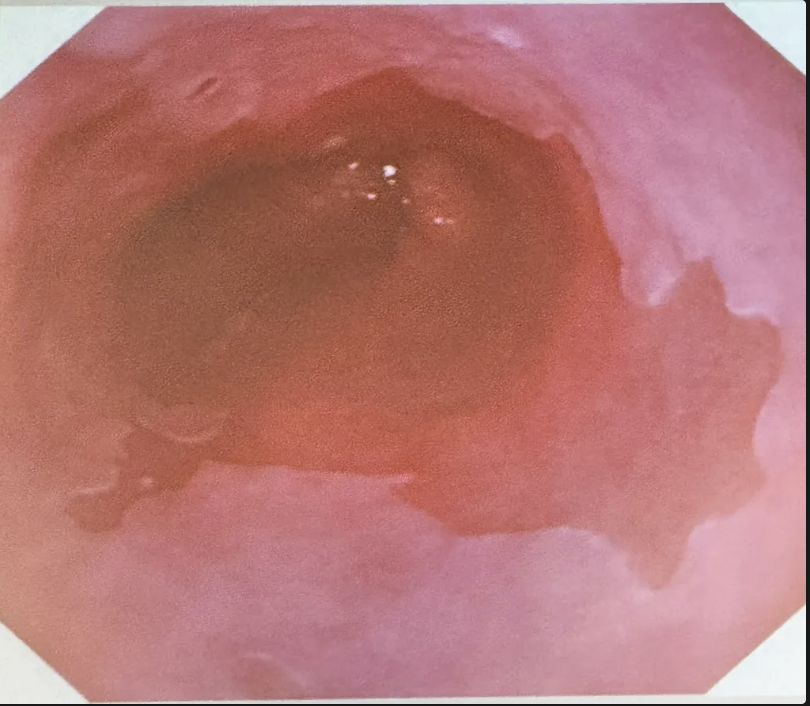

Clasificación **endoscópica de esofagitis**

- Grado A = una o más lesiones mucosas < 5 mm. - Grado B = lesión mucosa >5mm sin continuidad entre pliegues mucosos prominentes - Grado C = lesión mucosa con continuidad entre pliegues prominentes de varios pliegues, pero no circunferencial - Grado D = lesión mucosa circunferencial